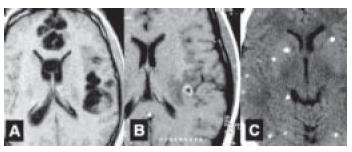

A doença demonstrada pelos exames de imagem é causada por